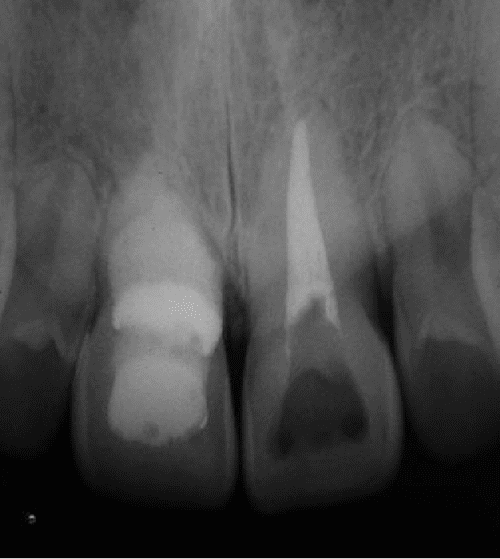

Figure 1 from Double 'pink tooth' associated with extensive internal What Happens If You Have A Pink Tooth You are looking at lesions that occur either internally or externally due to a resorptive process that results in significant loss of tooth structure. Periodontitis is a serious gum infection that damages the soft tissue and bone around teeth. A tooth infection, or dental abscess, can cause severe pain and discomfort, and may spread to other areas if untreated. Find. What Happens If You Have A Pink Tooth.

Figure 2 from Double 'pink tooth' associated with extensive internal What Happens If You Have A Pink Tooth Periodontitis is a serious gum infection that damages the soft tissue and bone around teeth. Dental resorption is the loss of parts of your tooth due to injury, infection, or other factors. Learn about the signs of a tooth infection spreading to other parts of the body, such as the brain, mediastinum, blood, and sinuses. Have you ever noticed a. What Happens If You Have A Pink Tooth.